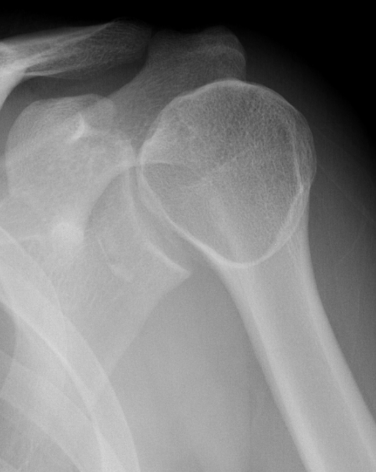

Scapular lateral

Center of the humeral head must be centered on the Y / Mercedes sign

Y is formed by

- coracoid anteriorly

- scapular spine posteriorly

- scapula body inferiorly

Normal scapular lateral

Posterior shoulder dislocation

Posterior shoulder dislocations